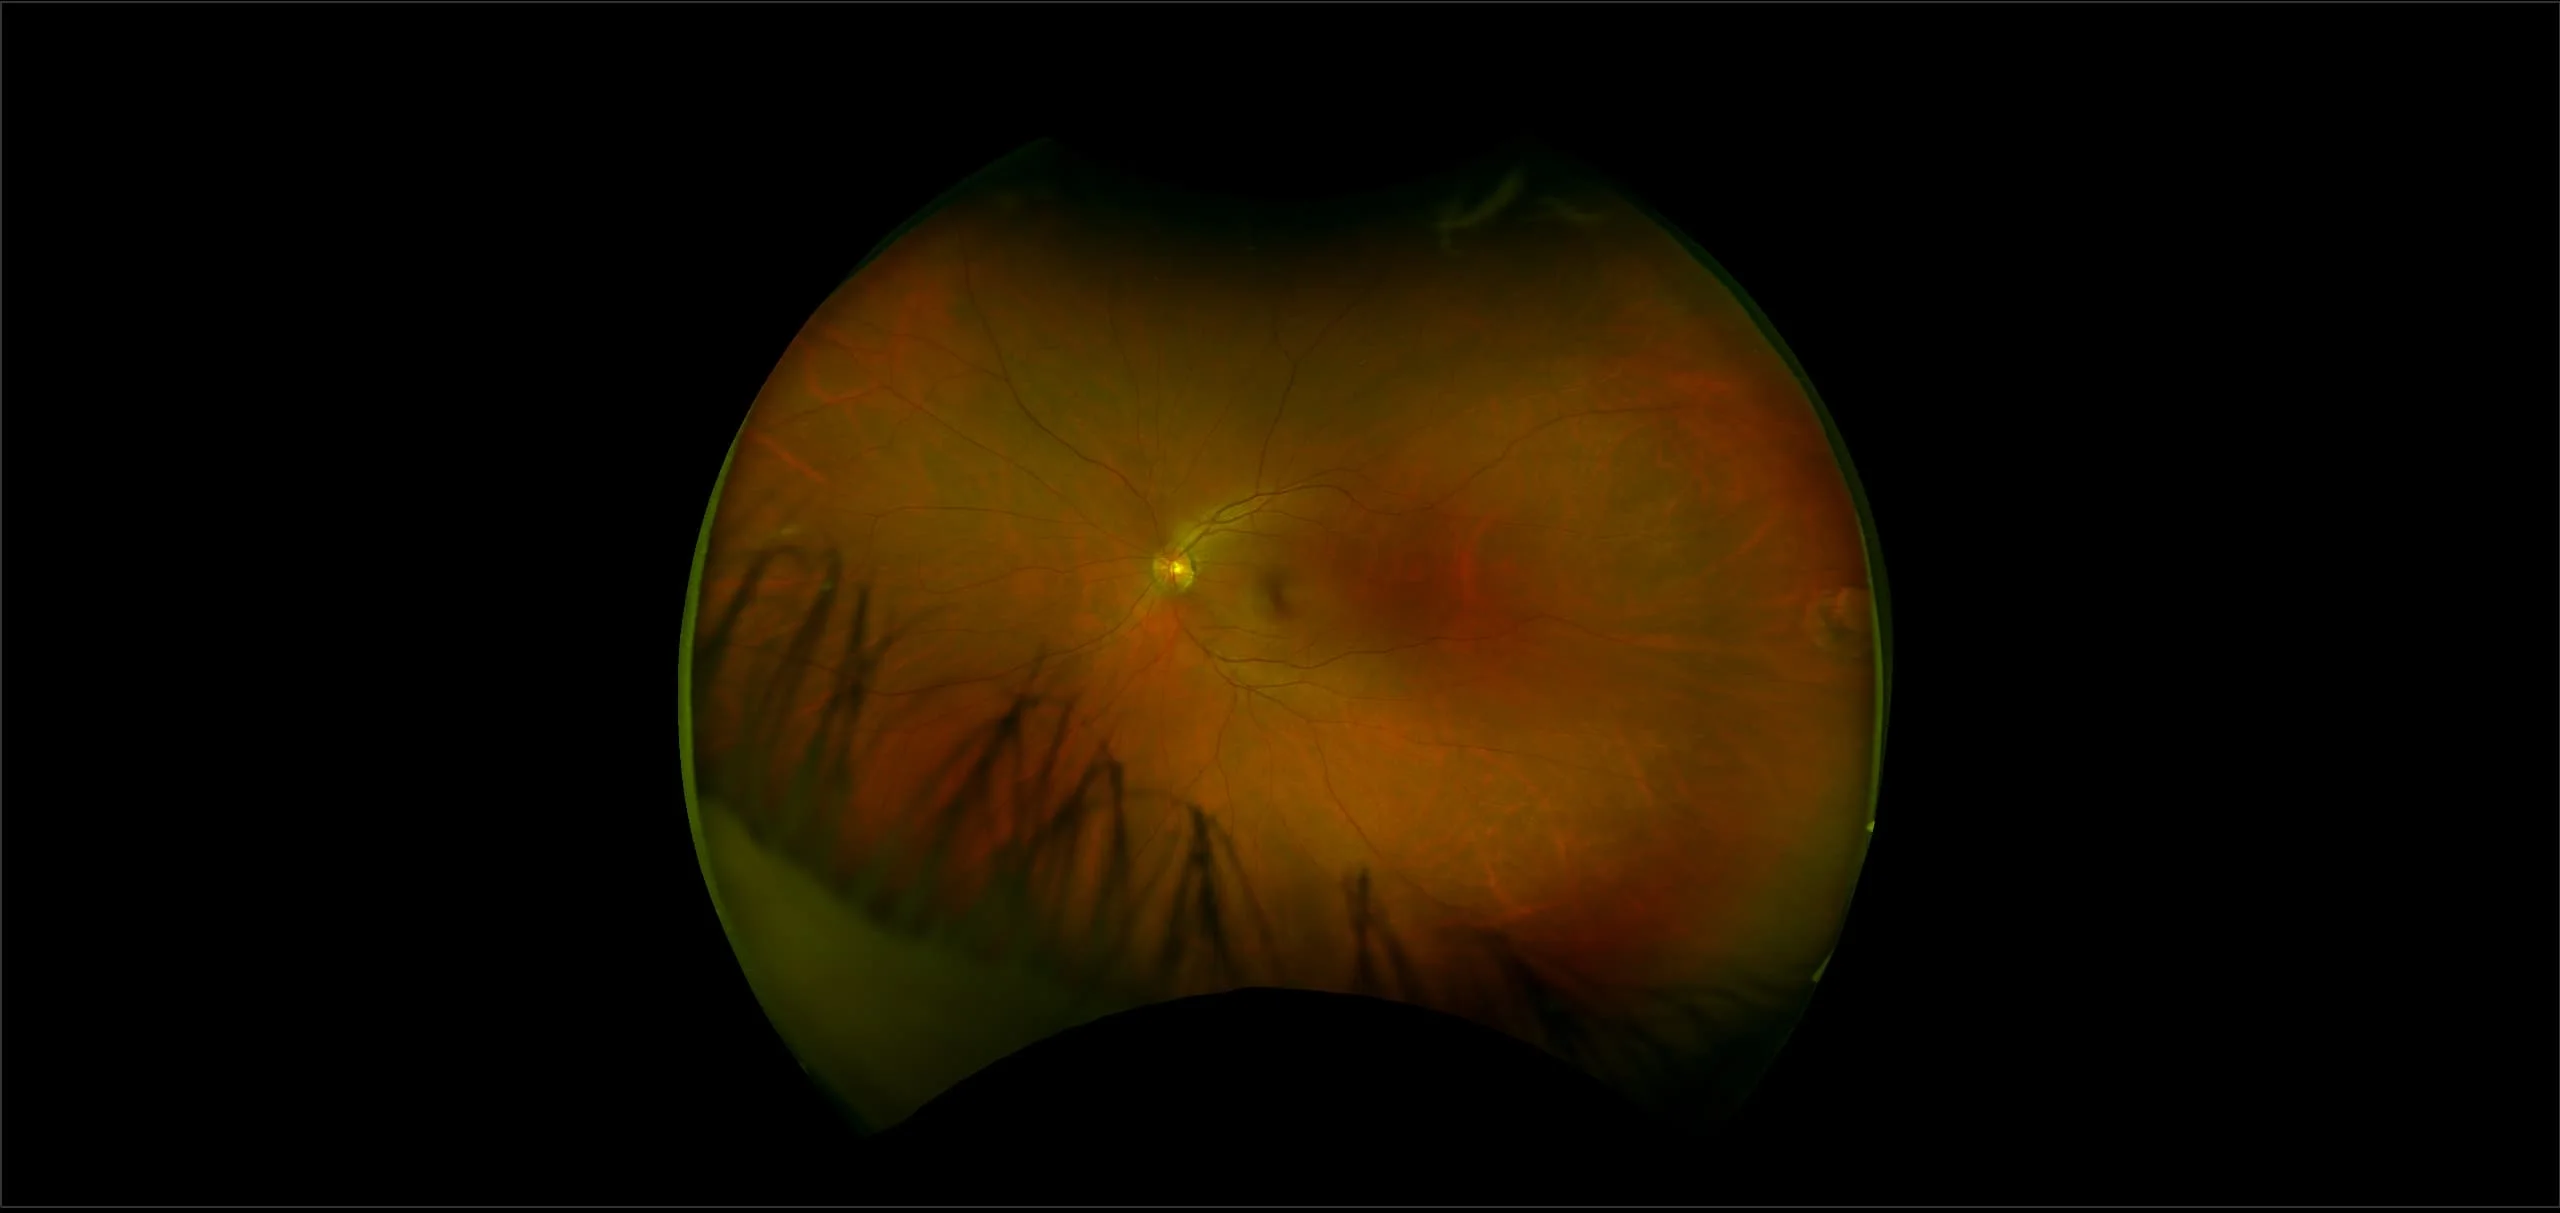

Retinal Atrophy

Retinal atrophy occurs when there is damage to the tissue in the retina that causes partial or total deterioration of your vision.